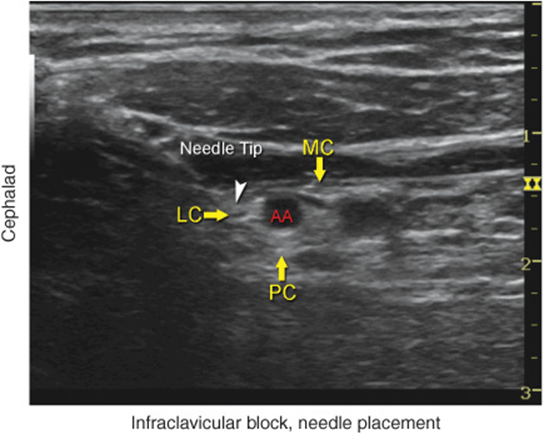

• Reverberation artifact posterior to the artery is often misinterpreted as the posterior cord. Figure 31-7 demonstrate such a dilemma where the structured labeled as posterior cord (PC) can easily represent a mere reverberation artifact.

FIGURE 31-7. An ultrasound image demonstrating an actual needle placement above (cephalad) the axillary artery (AA) and an injection of local anesthetic (2 mL; blue shadow) to document the proper needle tip placement. LC, lateral cord; MC, medial cord; PC, posterior cord.